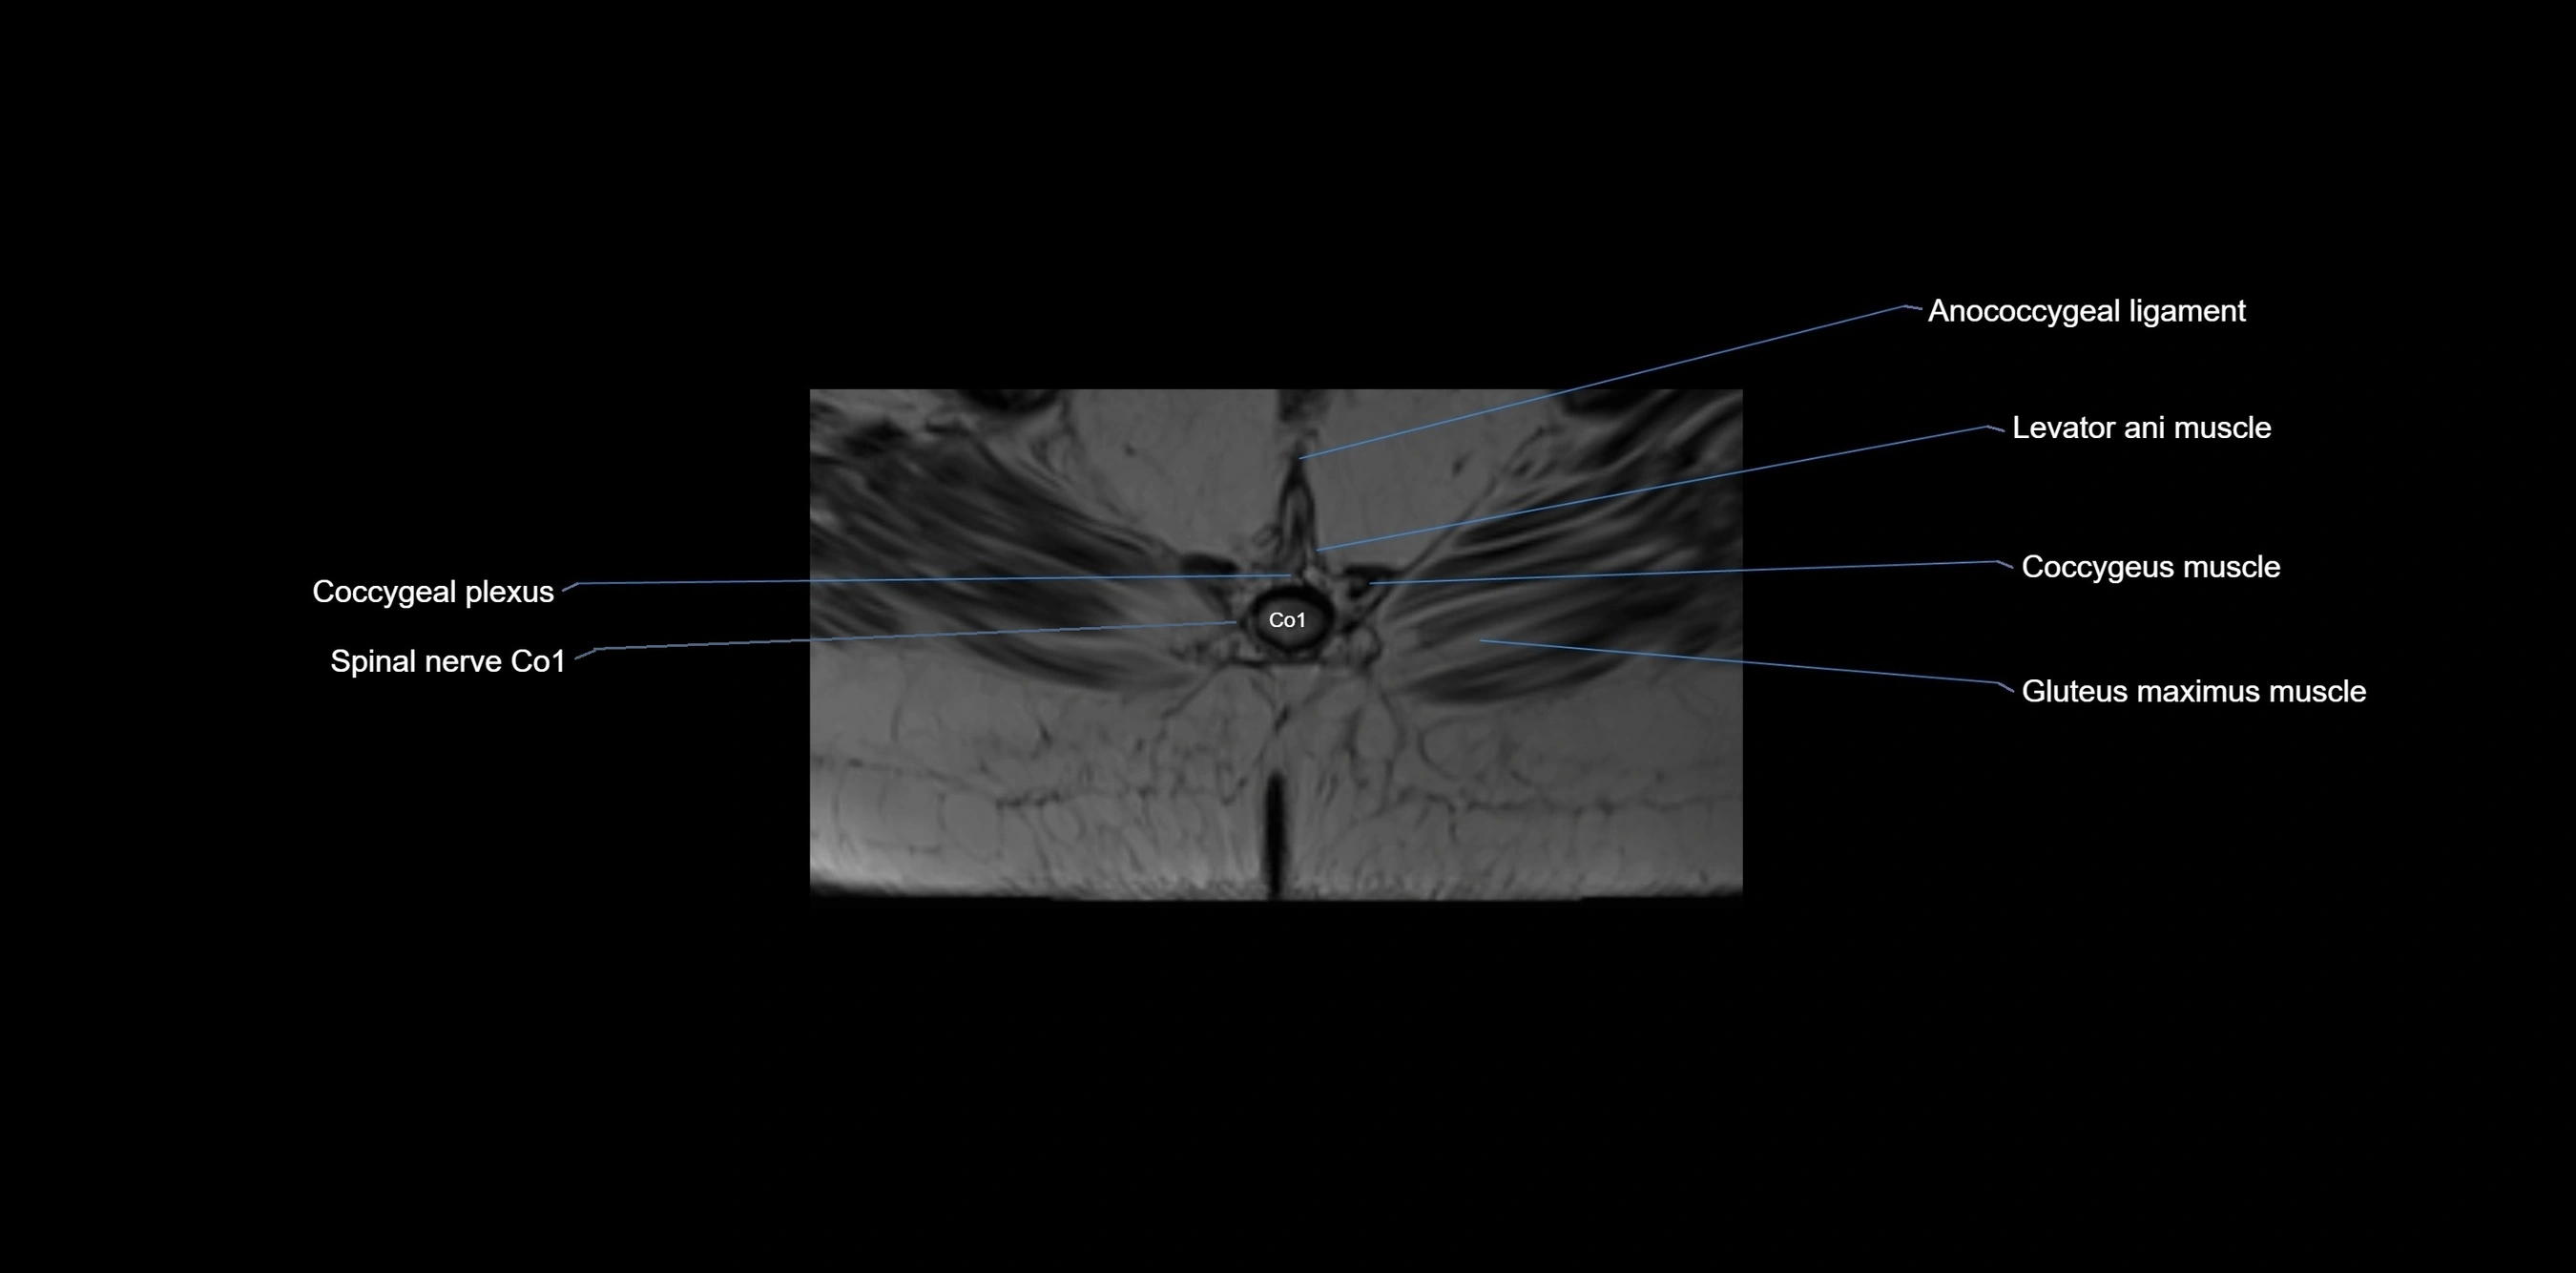

MRI image

image